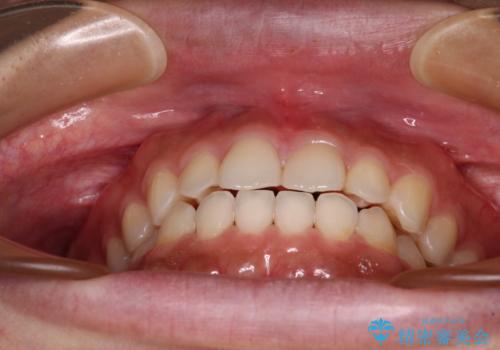

インビザラインを用いた上顎の部分矯正

- 上顎前歯の叢生を気にして来院された患者様です。

下顎前歯や上下奥歯の咬み合わせには殆ど問題がないため、上顎前歯のみを矯正する治療を提案しました。

ワイヤー装置でもインビザラインでも可能でしたが、前歯のみをきれいに排列するのであればインビザラインの方が仕上がりが良いので、インビザライン・ライトにて治療を行うこととしました。